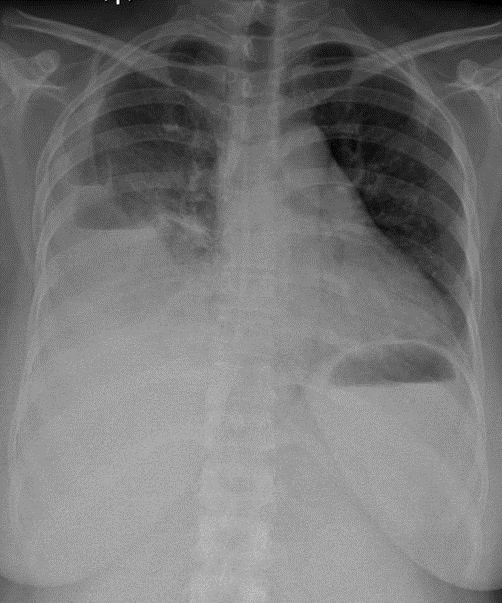

Hãy phân tích tình huống Nữ 37 tuổi

1-Thâm nhiểm thùy dưới hai phổi => VIÊM PHỔI 2-Tràn dịch + tràn khí màng phổi (P)